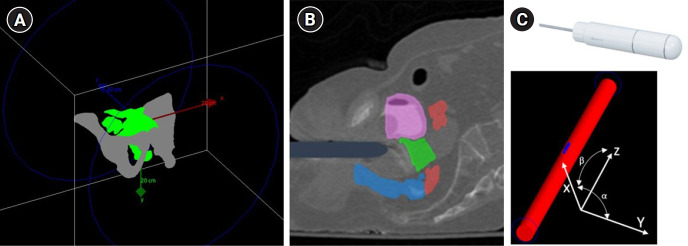

Purpose: Implementing intensity-modulated brachytherapy (IMBT) techniques with high-energy sources like 60Co has always been challenging due to the clinical limitations of the applicator dimensions. This study aims to investigate using tungsten trioxide nanoparticles/epoxy composite as a shielding material to enhance the protective properties of a redesigned applicator.

Materials and methods: The Geant4 application to tomographic emission, the Geant4-based Monte Carlo dose calculation engine (version 9.0), was used to simulate the shielding composite and the IMBT technique with a voxelated patient-based phantom. To evaluate the effectiveness of the new shielding material, IMBT plans created with the redesigned applicator were compared with those with a conventional applicator. 60Co and 192Ir were utilized, and in the same high-risk clinical target volumes D90, the D2cc for the bladder and rectum were evaluated in 18 patients with vaginal cancer.